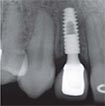

安卓健临床案例分享

安卓健种植产品销往全球100多个国家精密工程CFDA

权威认证,可放心使用。安卓健种植体手术程序简单,

更少创伤,更快恢复,更加安心。